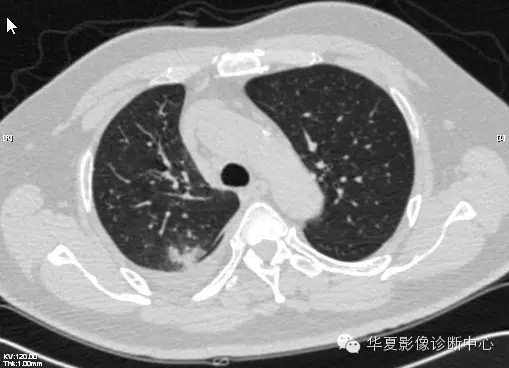

【病例学习】甲型H7N9禽流感一例

男性 63

发热咳嗽5天

2013-4-7CT进一步检查。

最终诊断:H7N9。